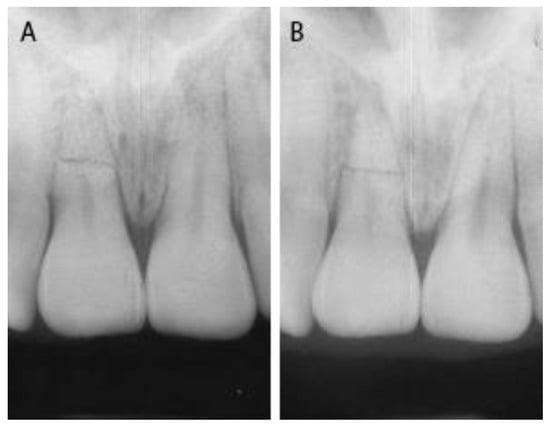

2. Case Presentation